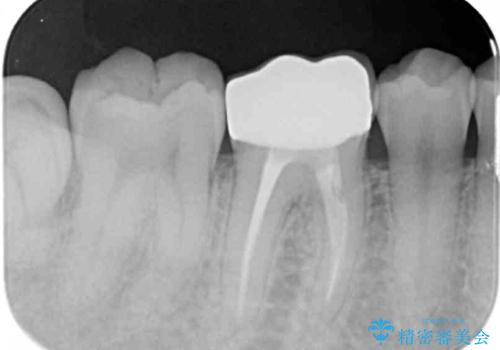

1. 放置してしまった虫歯の治療の治療前